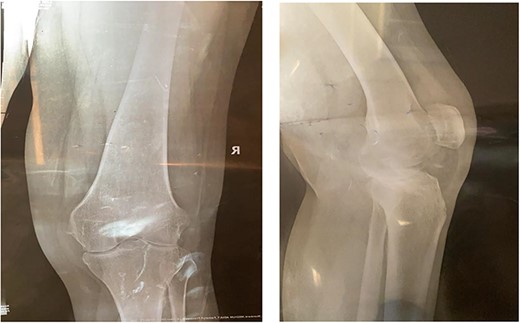

A 32-year-old female known case of rheumatoid arthritis affecting both knees presented to our clinic complaining of severe right knee stiffness post TKA 4-years-ago done in an outside facility (Figs. 1 and 2). She lives in a rural community and was on hydroxychloroquine, but her disease was active as she was not compliant to her medication. On physical examinations, the right knee was larger in size compared to the left knee without joint effusion. Range of motion was zero on flexion, −10° in extension. Standing knee X-ray showed HO around the prosthesis (Fig. 2). Computed tomography (CT) demonstrated extensive HO with implants fixed in place (Fig. 3). Revision surgery and replacement of the prostheses was considered to restore function.

Preoperative X-ray of the knee before the primary operation showing severe osteoarthritis changes.